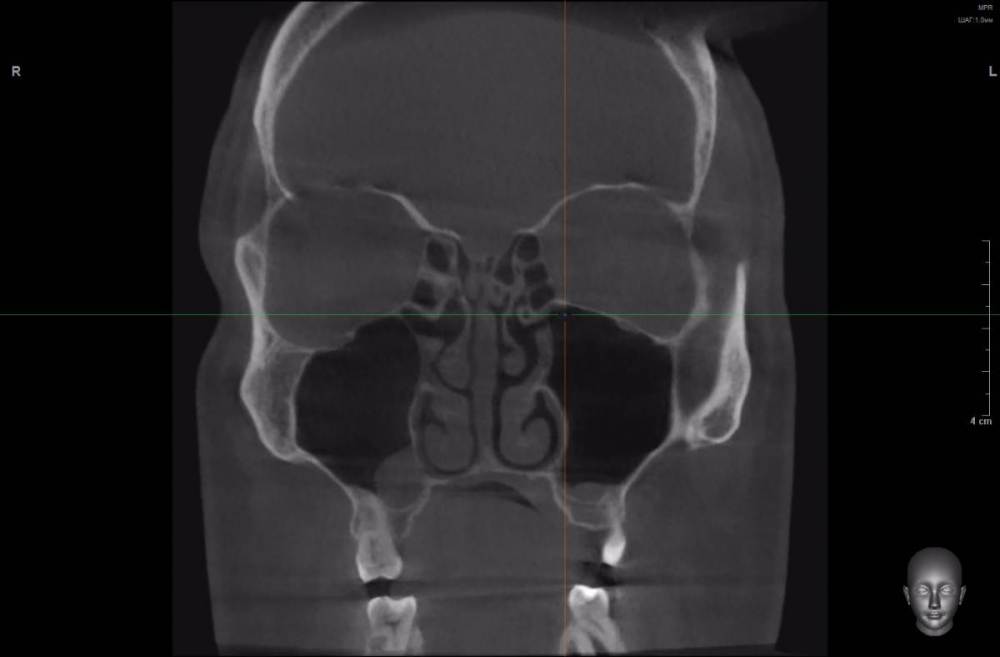

peter42 Опубликовано 10 декабря, 2021 Поделиться Опубликовано 10 декабря, 2021 (изменено) Доброго времени суток уважаемые доктора! Несколько лет назад (более 15) у меня был пульпит 6-го зуба (вверху слева), позже была безуспешная попытка его перелечить, в результате которой, зуб раскололся пополам и его пришлось удалить. Перелечивать зуб я пытался по тому, что после употреблении холодной пищи (или жидкости) у меня примерно через сутки начинались боли сначала в челюсти, в области левой пазухи в проекции над зубом, а спустя некоторое время болела уже вся голова. Также ощущалось чувство давления, набухания в этой области, усиливалась заложенность носа с левой стороны. При этом припухлости десны, выделений из носа (гной, слизь) не было, и сейчас тоже нет. Через год после удаления зуба, я был на приеме у парадонтолога, который направил меня на рентген (панорамный снимок), взглянув на снимок, он заметил, что корень зуба был удален не полностью - в челюсти остался корень. Позже этот корень мне благополучно удалили (тот же стоматолог- хирург). Однако уже прошло много лет, а все осталось как и до удаления - стоит мне снова простудиться или просто поесть мороженного (выпить даже не очень холодной воды), то через некоторое время (около суток) опять начинаются боли в верхней челюсти, болит голова, пенталгин и тот не всегда хорошо помогает снять боль. По рекомендации знакомых я обращался к другому стоматологу, который меня направил на" 3Д" КТ зубов. Посмотрев снимки он заключил, что в левой пазухе у меня тоже киста, и что это проявление гайморита. ЛОР посмотрев КТ сказал, что это кисты и они очень мелкие (ретенционные) имеют «зубную» природу, в связи с чем, давать такую болевую симптоматику не могут. Также я ходил на консультацию к неврологу, который по характеру боли (ноющая, не резкая, возникающая и прекращающаяся постепенно, присутствует ночью, не болит лицо) заключил, что причина скорее всего в зубах или в пазухе — круг замкнулся. На сегодня вся симптоматика сохраняется (боль, заложенность носа), болит в районе зуба 2,7 и 6-го удаленного зуба, сам склоняюсь, что болит все таки зуб 2,7 По совету знакомого почитал Ваш форум, сделал свежее «3Д» КТ зубов и пазух на аппарате «Ватек» в «Пикассо». Прошу Вас посмотреть КТ и дать совет, что мне предпринять, есть ли у меня стоматологические проблемы, вызывающие боли и другие симптомы? https://drive.google.com/drive/folders/1GXwLnOF5bPR5duemJODcfdSJHJyQORxC?usp=sharing Изменено 10 декабря, 2021 пользователем peter42 Ссылка на комментарий

peter42 Опубликовано 11 декабря, 2021 Автор Поделиться Опубликовано 11 декабря, 2021 Спасибо за ответ. Я в апреле оперировался у очень хорошего ЛОРа в Москве (перегородка, раковины), ему об этой проблеме тоже говорил, но он считает, что эта киста маленькая и "клинически не значима" (дословно) и трогать ее смысла нет. Интересно, что справа тоже есть кисты, но там нет такой проблемы. Кстати справа мне в 2011 г. кисту удаляли, но она снова выросла. В описании КТ рентгенолог указал на кариес в 2,7, как считаете, может ли он быть причиной пульпита и болей? Ссылка на комментарий